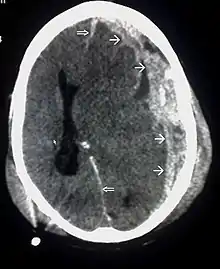

| CT scan showing cerebral contusions, hemorrhage within the hemispheres, and subdural hematoma. There is also displaced skull fracture of left transverse parietal and temporal bones.[2] | |